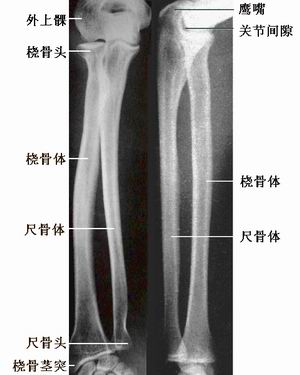

前臂骨的X线解剖 常规摄前后位、侧位片。前后位片上(图2),两骨并行,尺骨在内侧,桡骨在外侧。桡骨上端的桡骨头呈圆盘状,桡骨颈下方的内侧缘显示三角致密影为桡骨粗隆影。尺骨上端大而不规则,主要参与构成肘关节。尺骨下端变细,尺骨头内后侧有尺骨茎突影。前臂侧位片,尺、桡骨上、下两端都显示部分重叠,但骨干分开,桡骨干后缘和尺骨前缘之间显示长梭形空白区,为透亮的骨间膜。